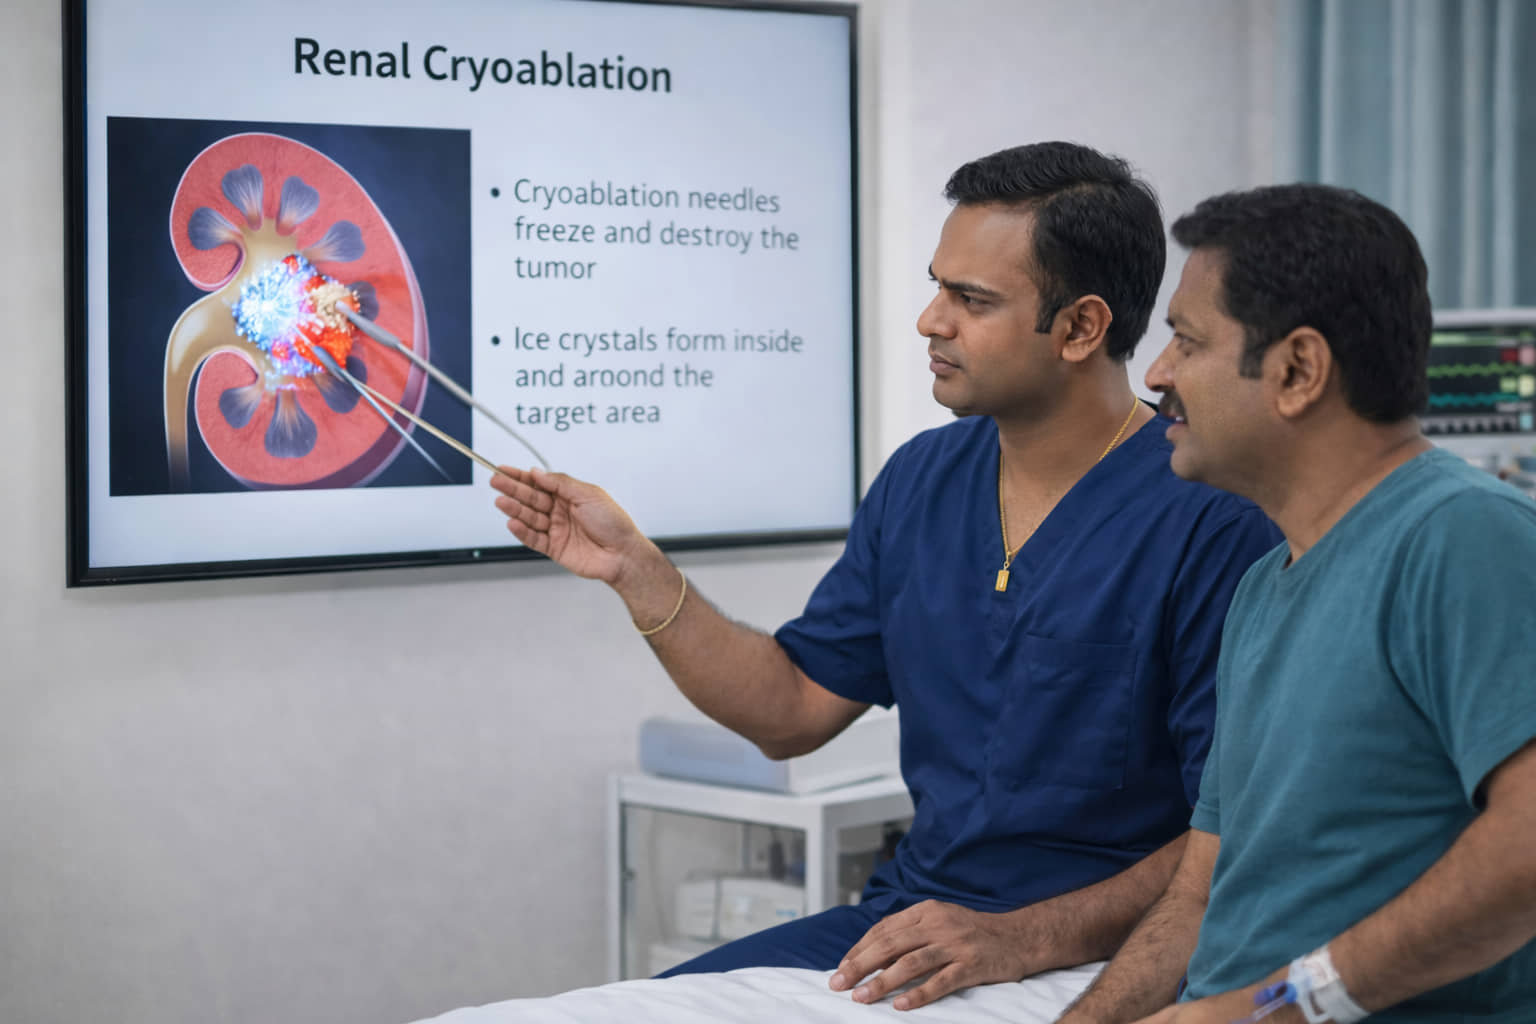

🩺 What Is Renal Cryoablation?

Renal Cryoablation is a cutting-edge, minimally invasive treatment that uses extreme cold to destroy cancerous cells while leaving the healthy part of the kidney intact.

🎯 How Cryoablation Works: The Power of Ice

Renal cryoablation is a minimally invasive procedure that uses extreme cold to destroy kidney tumors. It is often called a "no-cut" procedure because it is performed percutaneously (through the skin) using small needles rather than a surgical incision.

Here is a breakdown of how it works and why it is a vital "lifeline" for many:

1. How it Works

The "Pinhole" Access: An interventional radiologist uses live imaging (like a CT scan or ultrasound) to guide one or more thin, needle-like probes through the skin directly into the tumor.

The Freezing Cycle: Argon gas is circulated through the needles, creating an "ice ball" that reaches temperatures as low as -180°C. This extreme cold ruptures the cancer cells, destroying the tumor while it remains inside the body.

Natural Healing: After the procedure, the needles are removed and the body naturally absorbs the dead tumor tissue over time, leaving only a small amount of scar tissue.